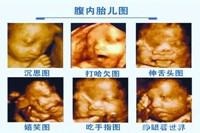

四維彩超是超聲檢查的一種,除了一般彩超的功能外,還可以進行胎兒頭面部立體成像,可清晰地顯示眼、鼻、口、下頷等狀態(tài),可協(xié)助醫(yī)生直接對胎兒先天畸形進行診斷,包括表面畸形、...